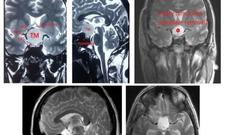

Unikal neyrocərrahiyyə əməliyyatı icra edilib